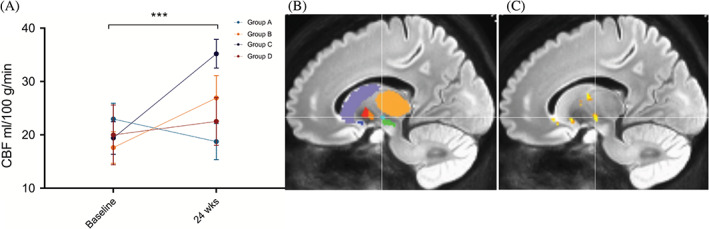

伪连续动脉旋转显示时间( P<0.001)和区域(P<0.001)的主效应显着,但半球( P=0.401)或队列(P=0.088) 的主效应不显着。所有基底神经节结构的灌注从基线到输注后24周总体增加。事后按区域时间比较显示,同种异体hMSC输注后,随时间变化的灌注增加最显着的是丘脑底核(图2)。

在OFF状态下测试时,所有患者的运动能力都得到改善(图 2)。 3A-D)。除了1名患者在输注后3周出现运动障碍并需要减少多巴胺,所有患者均在输注后24周维持其基线多巴胺能方案。最高剂量对降低UPDRS总分、UPDRS运动评分和H&Y评分具有最显着的效果。